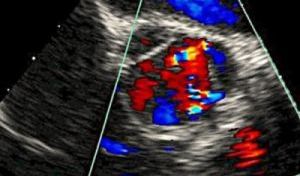

Pracownia USG |

Wykonywane są badania NFZ oraz odpłatne. Ultrasonografia jest jedną z nieinwazyjnych metod wykrywania zmian patologicznych w narządach. Badane USG pozwala na ocenę kształtu, wielkości i położenia narządu czy przestrzeni anatomicznej, a także powierzchni i wnętrza tych narządów. Wymagana wcześniejsza rejestracja.